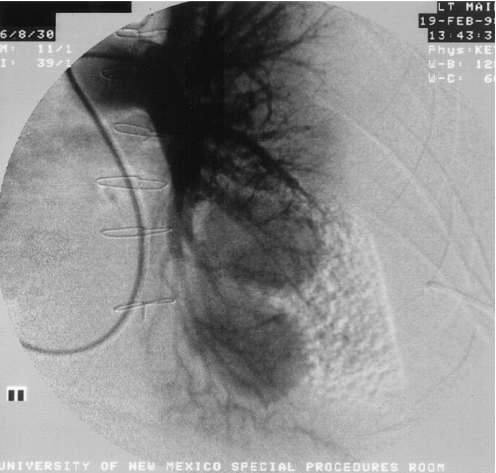

肺动脉假性动脉瘤(pulmonary artery pseudoaneurysms,PAPs)是⾎管损伤的并发症,感染、外伤、医疗操作等原因破坏了肺动脉⾎管壁,肺动脉膨胀所形成的圆形结构。与真性动脉瘤相比,假性肺动脉瘤更容易破裂出⾎,导致⼤咯⾎,甚⾄危及⽣命。下图是国外文献报道,可见肺动脉外周出现了PAPs,整个血管壁已被破坏,其原因是金黄色葡萄球菌感染[1]。图源:Ann Thorac Surg, 2003, 75(4):1332.